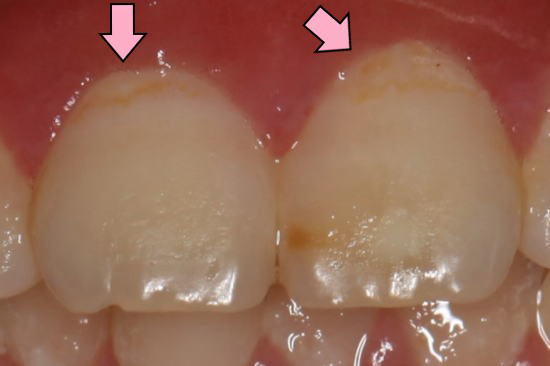

| 2015年12月14日:フッ素洗口開始して約4ヶ月半後 |

矢印の部分のむし歯(白濁)がなくなり、むし歯が消失(再石灰化)して きているのがわかります。 |